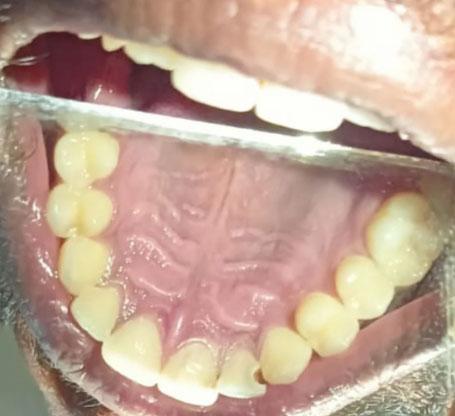

The image shows the lower anterior teeth (front bottom teeth) with visible crowding and misalignment. The teeth overlap slightly and appear rotated, indicating mild to moderate malocclusion.

-

Lower front teeth overlapping

Mild rotation of central incisors

Uneven incisal edges

Slight plaque accumulation near gumline

Gum tissue appears generally stable

No visible large cavities

No obvious fractures